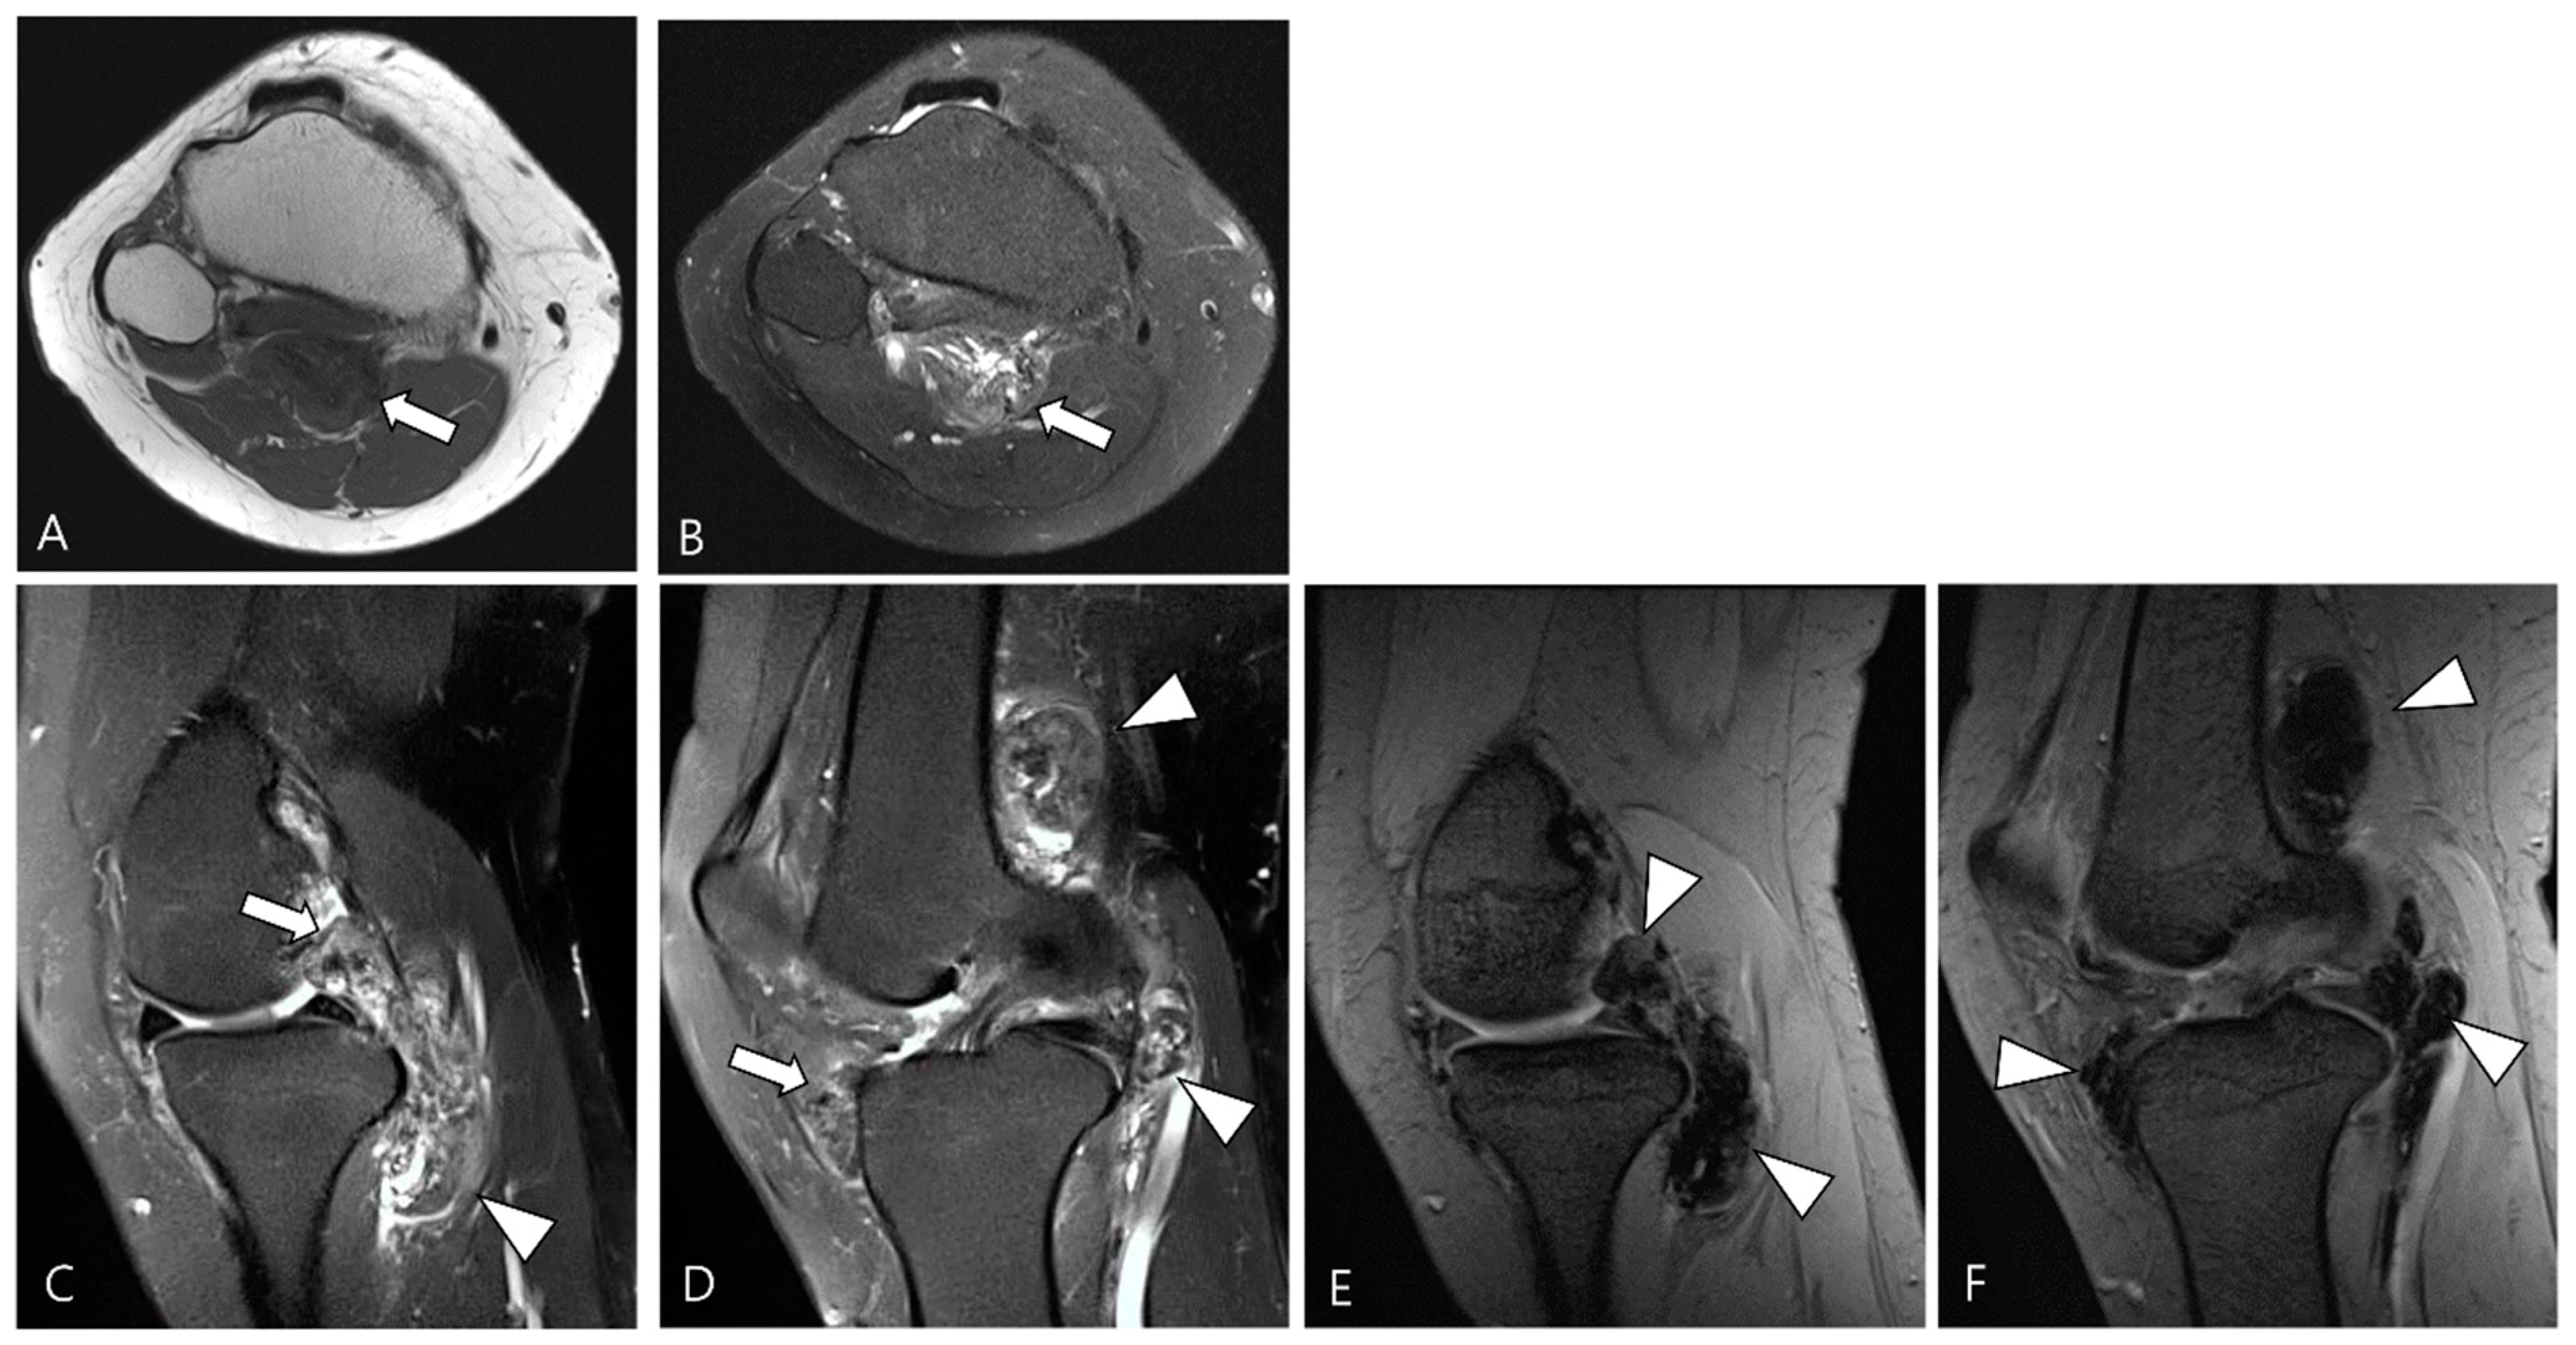

2.3. Morphological Findings for D-TSGCT

2.4. Relationship to Adjacent Structures of D-TSGCT